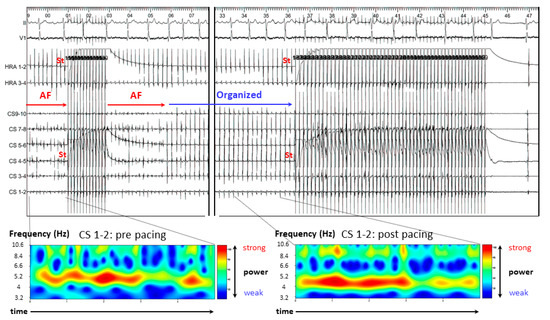

3.2. Representative Cases

3.2.1. Case 1: 42-Year-Old Man with Symptomatic PAF

3.2.2. Case 2: 72-Year-Old Man with Symptomatic PAF

3.2.3. Case 3: 67-Year-Old Man with Symptomatic PAF

2.5. Continuous Wavelet Transform (CWT) Analysis